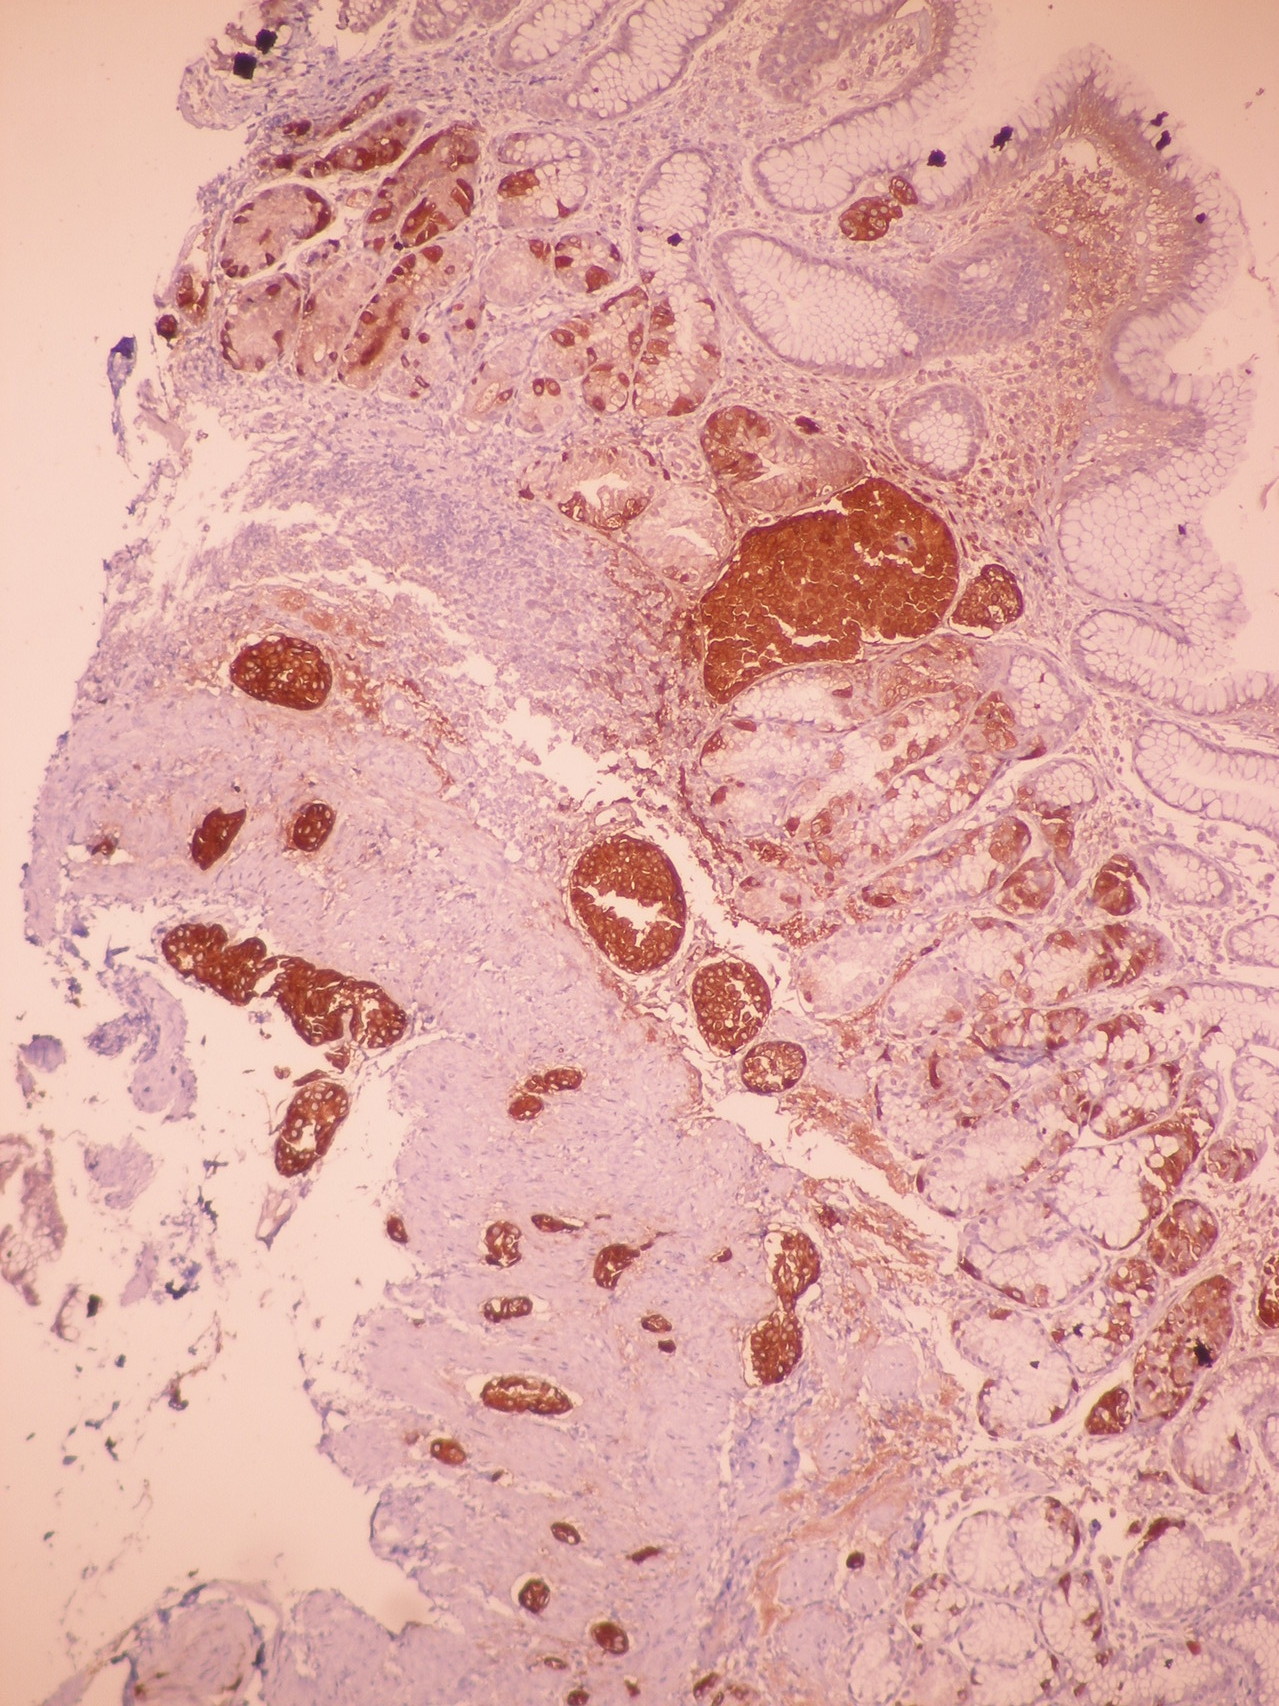

Patología Molecular

El diagnóstico sobre muestras de tejidos y líquidos corporales en plena era de la medicina del futuro, está basado en la integración de técnicas y conocimientos diferentes.

Hoy más que nunca es importante integrar una buena historia clínica con un correcto estudio de imagen y una buena morfología que además puede estar apoyada con proceso especiales complementarios relacionados con la Inmunología, Biología Molecular y Citogenética, generando así un estudio integral conocido como Patología Molecular.